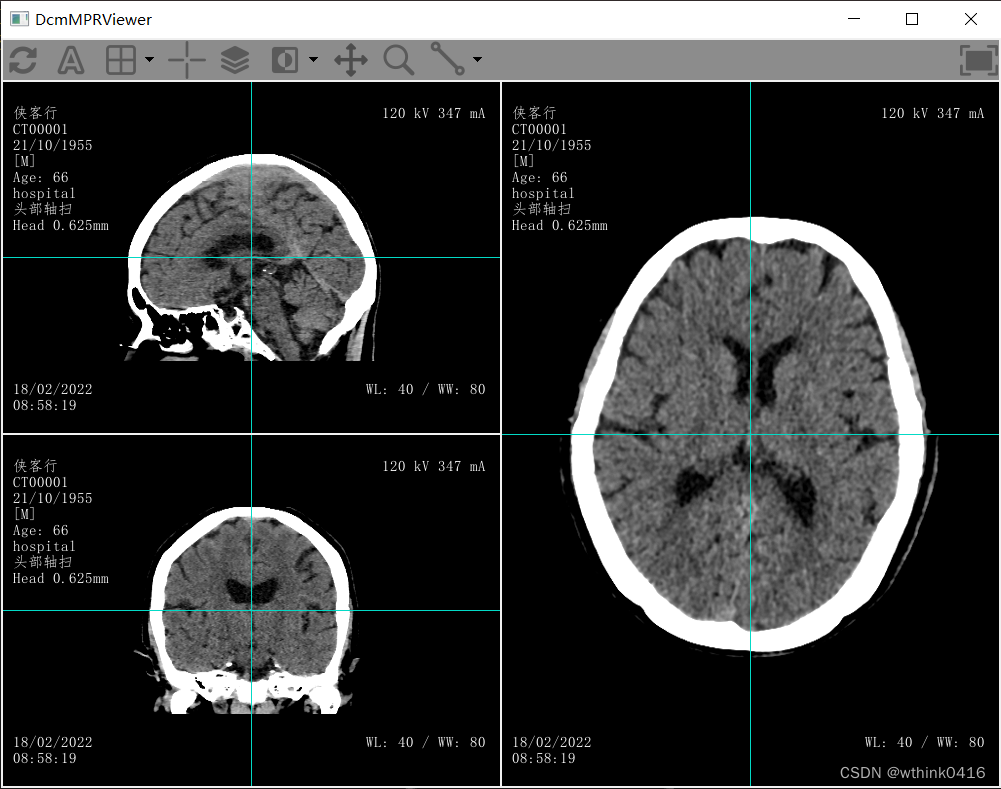

17、回到主窗口,点击![]() MPR图标,弹出MPR窗口,该窗口为独立窗口,可以同时选择其他序列进行多平面重建,方便进行对比

MPR图标,弹出MPR窗口,该窗口为独立窗口,可以同时选择其他序列进行多平面重建,方便进行对比

19、点击![]() 十字图标,可以隐藏和显示分割线

十字图标,可以隐藏和显示分割线

20、选中分割线,同时鼠标左键移动可以实现分割平面的旋转,或者选中分割线的焦点,同时鼠标左键移动可以调整分割平面的中心位置